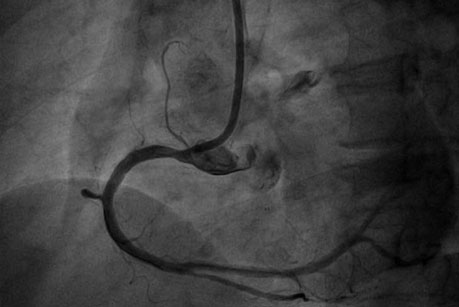

患者为老年女性,冠脉造影显示:右冠状动脉严重狭窄,伴有极为严重的钙化,需要行冠状动脉旋磨术治疗。但该患者血管发育极为粗大,直径在4mm以上,需要超大直径的旋磨头。目前国内常用的旋磨头直径为1.25-1.75mm, 配备2.0mm及以上旋磨头的医院很少。研究显示,我国女性仅有40%可以耐受7F鞘管(2.85mm),很少能容纳8F的鞘管(直径3.22mm)。但该患者需要超大直径旋磨头治疗,因此也需要大直径的8F指引导管和鞘管输送。

经过冠脉介入团队充分讨论后,制定了个体化的介入治疗方案,择期为患者进行冠状动脉旋磨术。心内科执行主任赵慧强将友谊医院通州院区备好的2.0mm和2.15mm旋磨头调至我院,亲自为患者进行介入治疗。他采用了自己首创的球囊辅助(BAT)的无鞘技术,经桡动脉成功将8F导管送至冠脉开口,先后使用2.0mm和2.15mm旋磨头进行旋磨,最终成功植入2枚支架,手术顺利完成,效果非常满意。患者目前已康复出院。